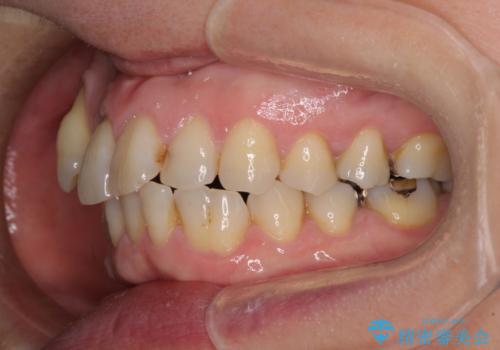

- 長年前歯の歯並びで悩んでいるとのことで来院された患者様です。

機能的なことを考えると八重歯となっている犬歯は抜歯せず、歯列を改善することが望ましいとされますが、数十年もの間犬歯がない咬み合わせで問題なく過ごしてきたため、八重歯を抜歯することで、手っ取り早く歯列を改善することとしました。